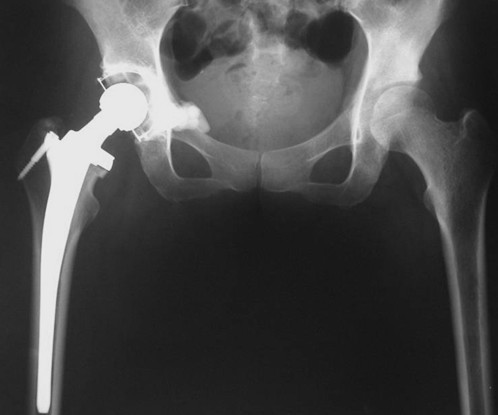

Ⅲ型:髋臼内壁、顶部及外侧壁均破坏。仅使用带翼网杯的全髋假体是不够的。在这种情况下,需要在骨盆缺损处放置数根斯氏针以便于将位于解剖位置的髋臼假体所承受的应力传导至脊柱(1-3)。在大多数髋臼周围破坏广泛的病例,需要采用扩大的髂股骨切口入路,以便于探查骨盆内外侧区域。在显露清楚后,自髋臼缺损处沿残留的正常髂骨向骶髂关节方向钻入2-3根斯氏针,并越过关节达到骶骨。应采用较粗的斯氏针,术中还需要X线监测以保证斯氏针的位置。在钻入斯氏针的同时,应用手指触摸坐骨切迹,以保证斯氏针的方向,防止其穿入骨盆内壁。当髋臼缺损较大时,还可以自前部髂嵴向前柱的耻骨及后柱的坐骨钻入更多的斯氏针做进一步的加强。在髋臼假体顶部切断斯氏针,并安装带翼网杯,在髋臼深部可以用金属钛网加强骨水泥固定。术后病人可全部负重行走,但需置患肢外展中立位约4周时间以防止脱位。也有采用马鞍式假体置换的报道, Benevenia等对20例髋臼III型转移瘤患者进行了马鞍假体置换,术后MSTS 93评分平均16.6分,多数病人可以扶拐行走(5)。对于髋臼上壁及内、外侧壁均破坏的HarringtonIII型患者,本组病例中,有7例患者采用了肿瘤刮除后、于骶髂关节处植入3-4枚斯氏针, 骨水泥填充髋臼上壁骨缺损,水泥型全髋重建髋关节。其中,有2例患者出现下地后髋部痛疼,负重时髋部不稳定。考虑为负重时骶骨内斯氏针承受较大剪力, 出现髋关节不稳。因此,在本组病例中,我们对4例Ⅲ型患者实施了整块切除、可调式人工半骨盆置换术。术后6周患者可以扶拐下地行走。平均MSTS93评分为23.3分。

图4,女,52岁,乳腺癌髋臼转移, Harrington III型